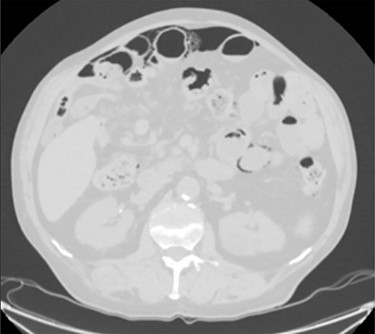

Unfortunately, once he returned home his temperature started to rise up to 38°C and he was readmitted to the hospital. A new contrast-enhanced Chest/Abdomen CT showed a bilateral pneumonia and a massive amount of intraperitoneal free gas, mainly in the abdominal upper quadrants (Fig. 2). No fat stranding, nondilated bowel, no vascular abnormalities and no free fluid were detected. Although the CT showed an evident worsening, the patient still remained completely asymptomatic on physical examination. Accordingly, he started to be treated with meropenem for pneumonia (Escherichia coli was isolated into the sputum) and he finally agreed to underwent diagnostic laparoscopy. Surprisingly, that was definitely not a case of pneumoperitoneum but an idiopathic PCI as we found multiple intramural air content cyst, about 2–3 cm in diameter, all around the small bowel loops and mesentery (Fig. 3). No intra-abdominal maneuvers were made. The patient had an unremarkable recovery (Clavien–Dindo classification grade was 1) [3] and he was discharged home on postoperative Day 15 in well condition, once he had recovered from pneumonia.

PCI was ultimately identified retrospectively using lung window settings.